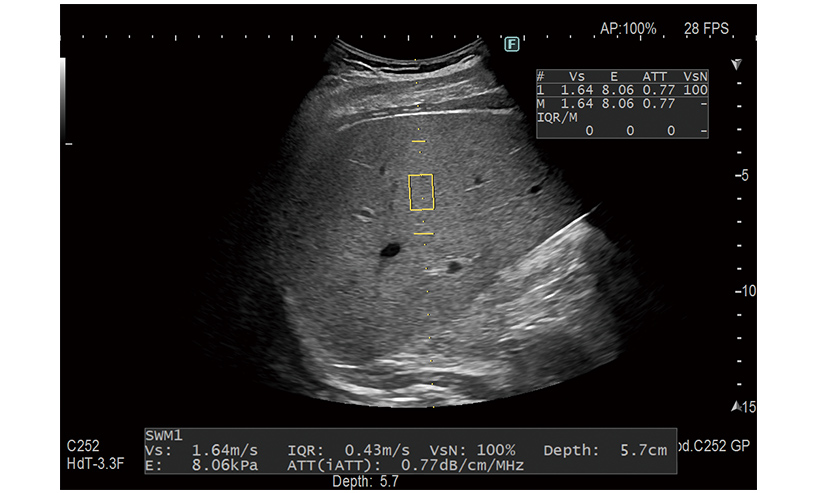

It is possible to evaluate tissue stiffness by generating shear waves and measuring Vs, its propagation velocity in the tissue.

An index to estimate the degree of hepatic adipogenesis (ATT) can also be measured at the same time.